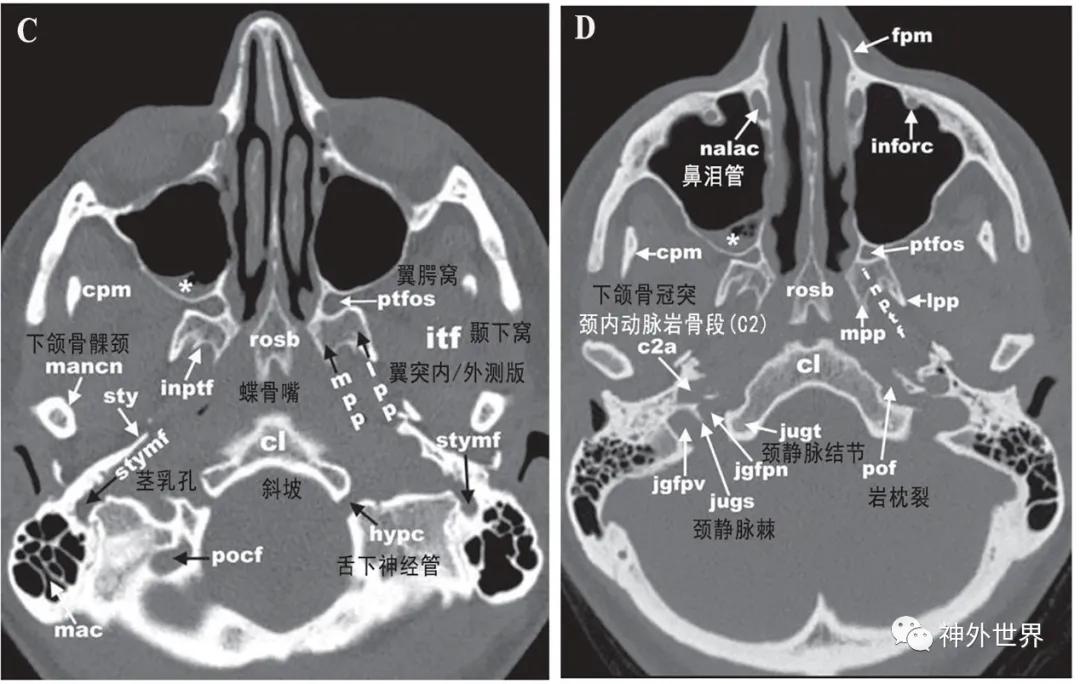

图3:颅底CT骨性横断面影像解剖